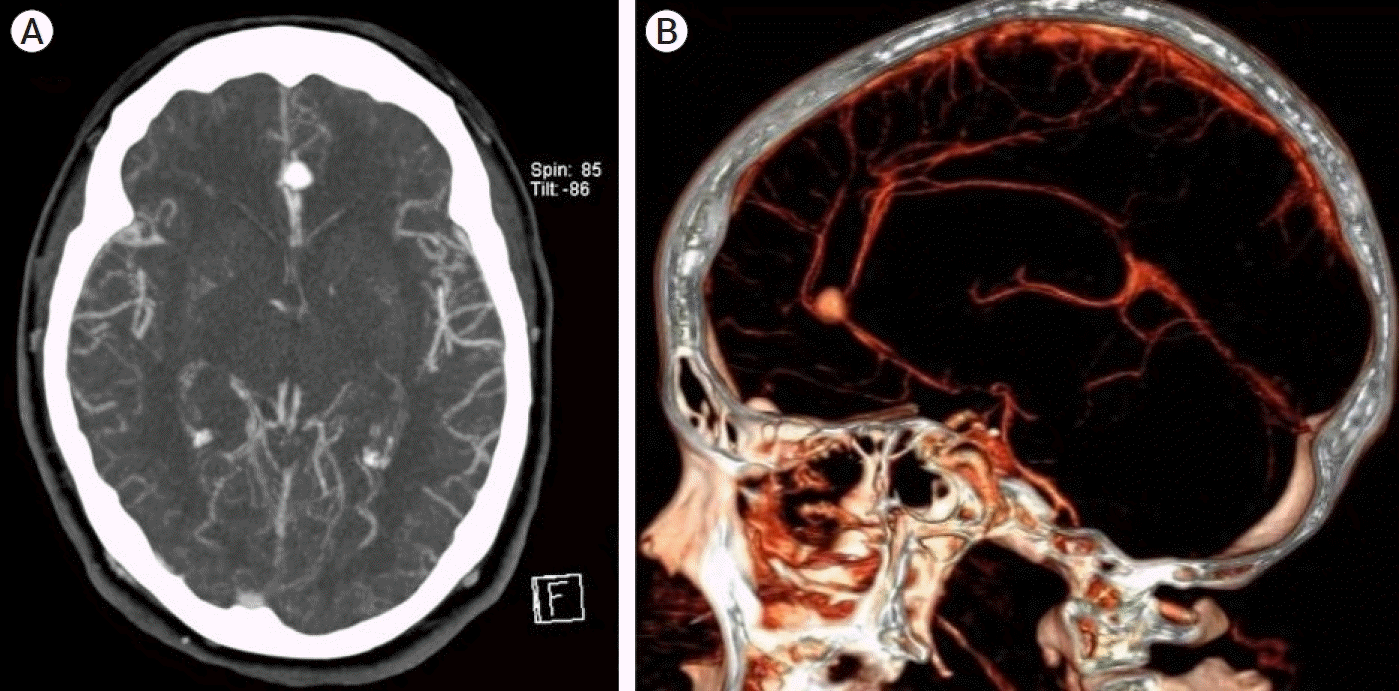

A surgical procedure was deemed necessary following the clinical condition and imaging findings. During surgery, the patient was supine with the head fixed on a Mayfield-Kees head holder in a neutral position. A bifrontal craniotomy with a conventional anterior interhemispheric approach was performed. Under the microscopic vision, cerebrospinal fluid was depleted while opening the interhemispheric fissure. To improve the surgical vision, we removed the right frontal and interhemispheric hematoma, identifying both A2 arteries and using a temporary clip in the left A2 artery to achieve aneurysm dome dissection. The aneurysm was attached to the callosomarginal branches and was thoroughly dissected with microsurgical techniques, identifying the neck and the distal segment of the left anterior cerebral artery. A 7 mm straight clip (Aesculap, PA, USA) was applied to the aneurysm’s neck. Posteriorly, the patency of the left A3 segment was verified with intravenous fluorescein, and no flow was observed through this artery (Fig. 2). An intra-aneurysmatic thrombus was observed through the aneurysm wall, explaining the flow obstruction. We decided to place a proximal temporary clip in the left A2 segment, and the aneurysm dome was opened linearly using a microscissor, corroborating the formation of an intra-aneurysmatic thrombus as a complication after clipping. The thrombus was located inside the aneurysm and a partly extended towards the DACA’s lumen. MIaT was performed using continued saline solution irrigation for the thrombus dissolution and microdissectors and microforceps to separate the thrombus from the vessel wall following a circumferential dissection (Figs. 3 and 4). We identified a small rupture on the aneurysm’s neck, where we put a 3 mm straight miniclip (Aesculap, PA, USA). The previous 7 mm straight clip was repositioned on the aneurysm’s neck, achieving a complete occlusion of the aneurysm. Once again, the patency of the left A3 segment was verified using intravenous fluorescein. Craniectomy in this patient was deemed necessary due to brain edema. A postoperative CTA scan was performed for adequate corroborating flow in both DACAs (Fig. 5). During the postoperative course, the patient’s consciousness and left hemiparesis improved 4/5 with sequel right central facial palsy. Follow-up was performed during the first month and posteriorly every three months at clinics.

Fig. 2.

(A) Intraoperative images showing the DACA aneurysm clipping with a 7 mm straight clip. (B) Patency of the left pericallosal artery was verified with intravenous fluorescein and no flow was observed. DACA, distal anterior cerebral artery